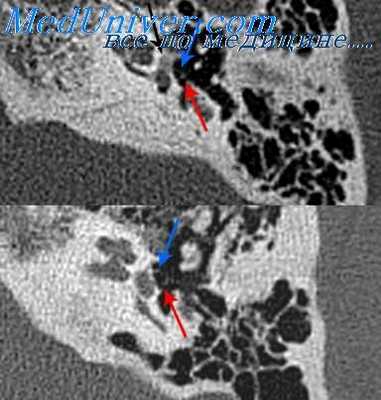

(Слева) При аксиальной КТ правой височной кости у молодого взрослого с прогрессирующей кондуктивной тугоухостью визуализируется типичная отоспонгиозная бляшка (фенестральный отосклероз) спереди от овального окна в области предполагаемой локализации щели перед окном.

(Справа) При корональной КТ правой височной кости у пациента со смешанной тугоухостью визуализируется рентгенонегативное «гало» вокруг улитки, обусловленное кохлеарным отосклерозом. Обратите также внимание на сопутствующий фенестральный отосклероз.